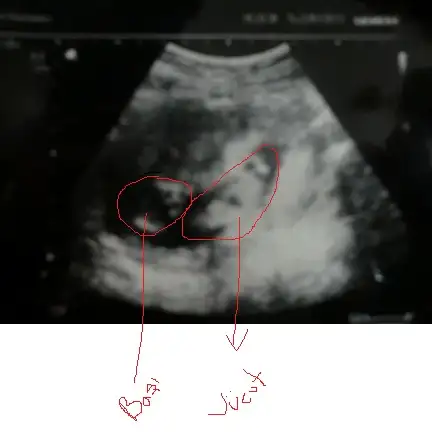

doğru mu işaretledim,bakarmısın canım?Yordum da seni bugün,kusura bakma canım)

Valla cnm senin bebek kiz cikarsa bayaa sasiririm ikinci resme dikkatle bak resmen yukari bakiyor cikinti

ki 12 haftalik galiba orada yinede resimdir dr larimiz daha iyi bilir elbet

cikinti var canim var da paralel yani kizz ama 11. hafta en yaniltan hafta 13 ve 12 varsa onlari koy